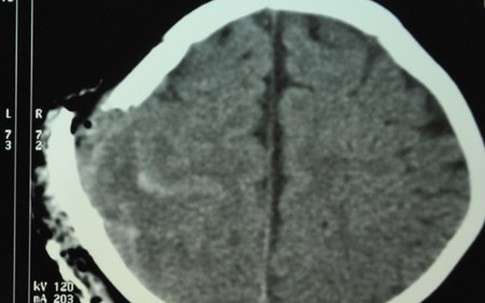

Hai bà bầu chấn thương não sau tai nạn nghi vấn

Xã hội

Trên đường từ nhà máy trở về nhà, hai chị em dâu ở chung nhà và cùng đang mang thai bị ngã xe máy, phải nhập viện trong tình trạng chấn thương sọ não. Một người đã tử vong, người còn lại đang nguy kịch.

Bố chơi trò tung hứng, bé bị quạt trần chém vào đầu

Gia đình

Thấy con cười nắc nẻ khi được tung lên, người bố cao hứng tiếp tục ném quá cao khiến đầu bé va vào cánh quạt đang quay.